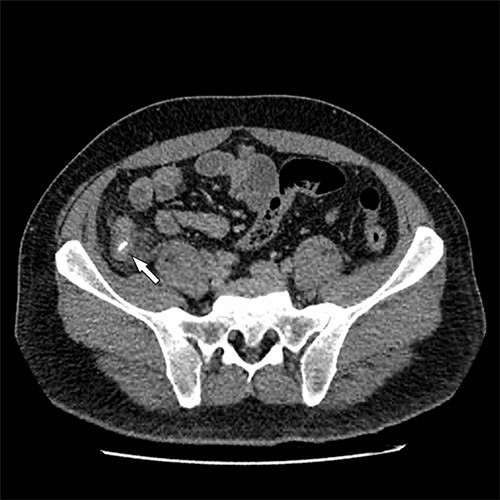

A 41-year-old, previously well, male presented to the emergency department with lower abdominal pain, pyrexia with a temperature of 38.2°C and a palpable suprapubic mass. His relevant background history included an uneventful laparoscopic appendicectomy 2 years prior for acute appendicitis, insulin independent type 2 diabetes and hypertension. He presented with raised inflammatory markers and computed tomography (CT) showing a well circumscribed central pelvis lesion that appeared concerning for a urachal malignancy (Fig. 1). This lesion was closely associated with the dome of the bladder (Fig. 2). This supracystic lesion measured 58 mm × 56 mm with central cystic component of 15 mm in diameter, and contained a 11 mm central calcification. Further characterization with magnetic resonance imaging showed possible extension of this mass to the rectus abdominis without significant lymphadenopathy (Fig. 3). Flexible cystoscopy only found inflammation at the dome. As urachal malignancy could not be unequivocally excluded on imaging studies alone, following multidisciplinary discussion, the decision was made to perform an excision of this lesion.

Sagittal CT cystogram. Arrowhead indicates involvement of anterior abdominal wall. Arrow indicates association of lesion with the dome of the bladder.